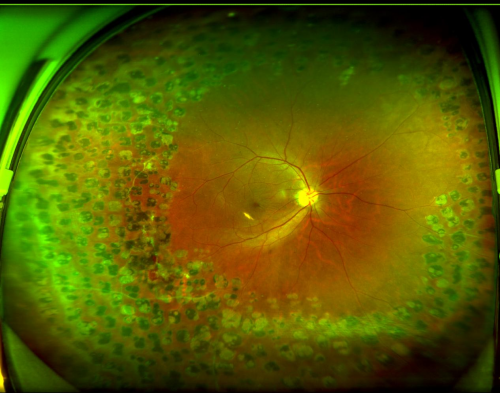

图:张先生右眼眼底

“因双眼在外院做过多次视网膜激光光凝术,视网膜周边形成了多量点状激光瘢痕。这些瘢痕与正常视网膜粘连紧密,大大增加了手术的复杂性和风险。对主刀医生的技术要求高——需要更丰富的经验、更精湛的显微手术技术,以及应对复杂组织变化的能力。”

2026年1月20日,赵铁英院长为张先生顺利实施了“右眼微创玻璃体视网膜病变手术+黄斑前膜、内界膜剥离术+气体填充术”。

术后恢复期间,张先生右眼的视物变形逐渐消失。2月24日复查时,视力已提升至0.8,视觉质量明显改善。